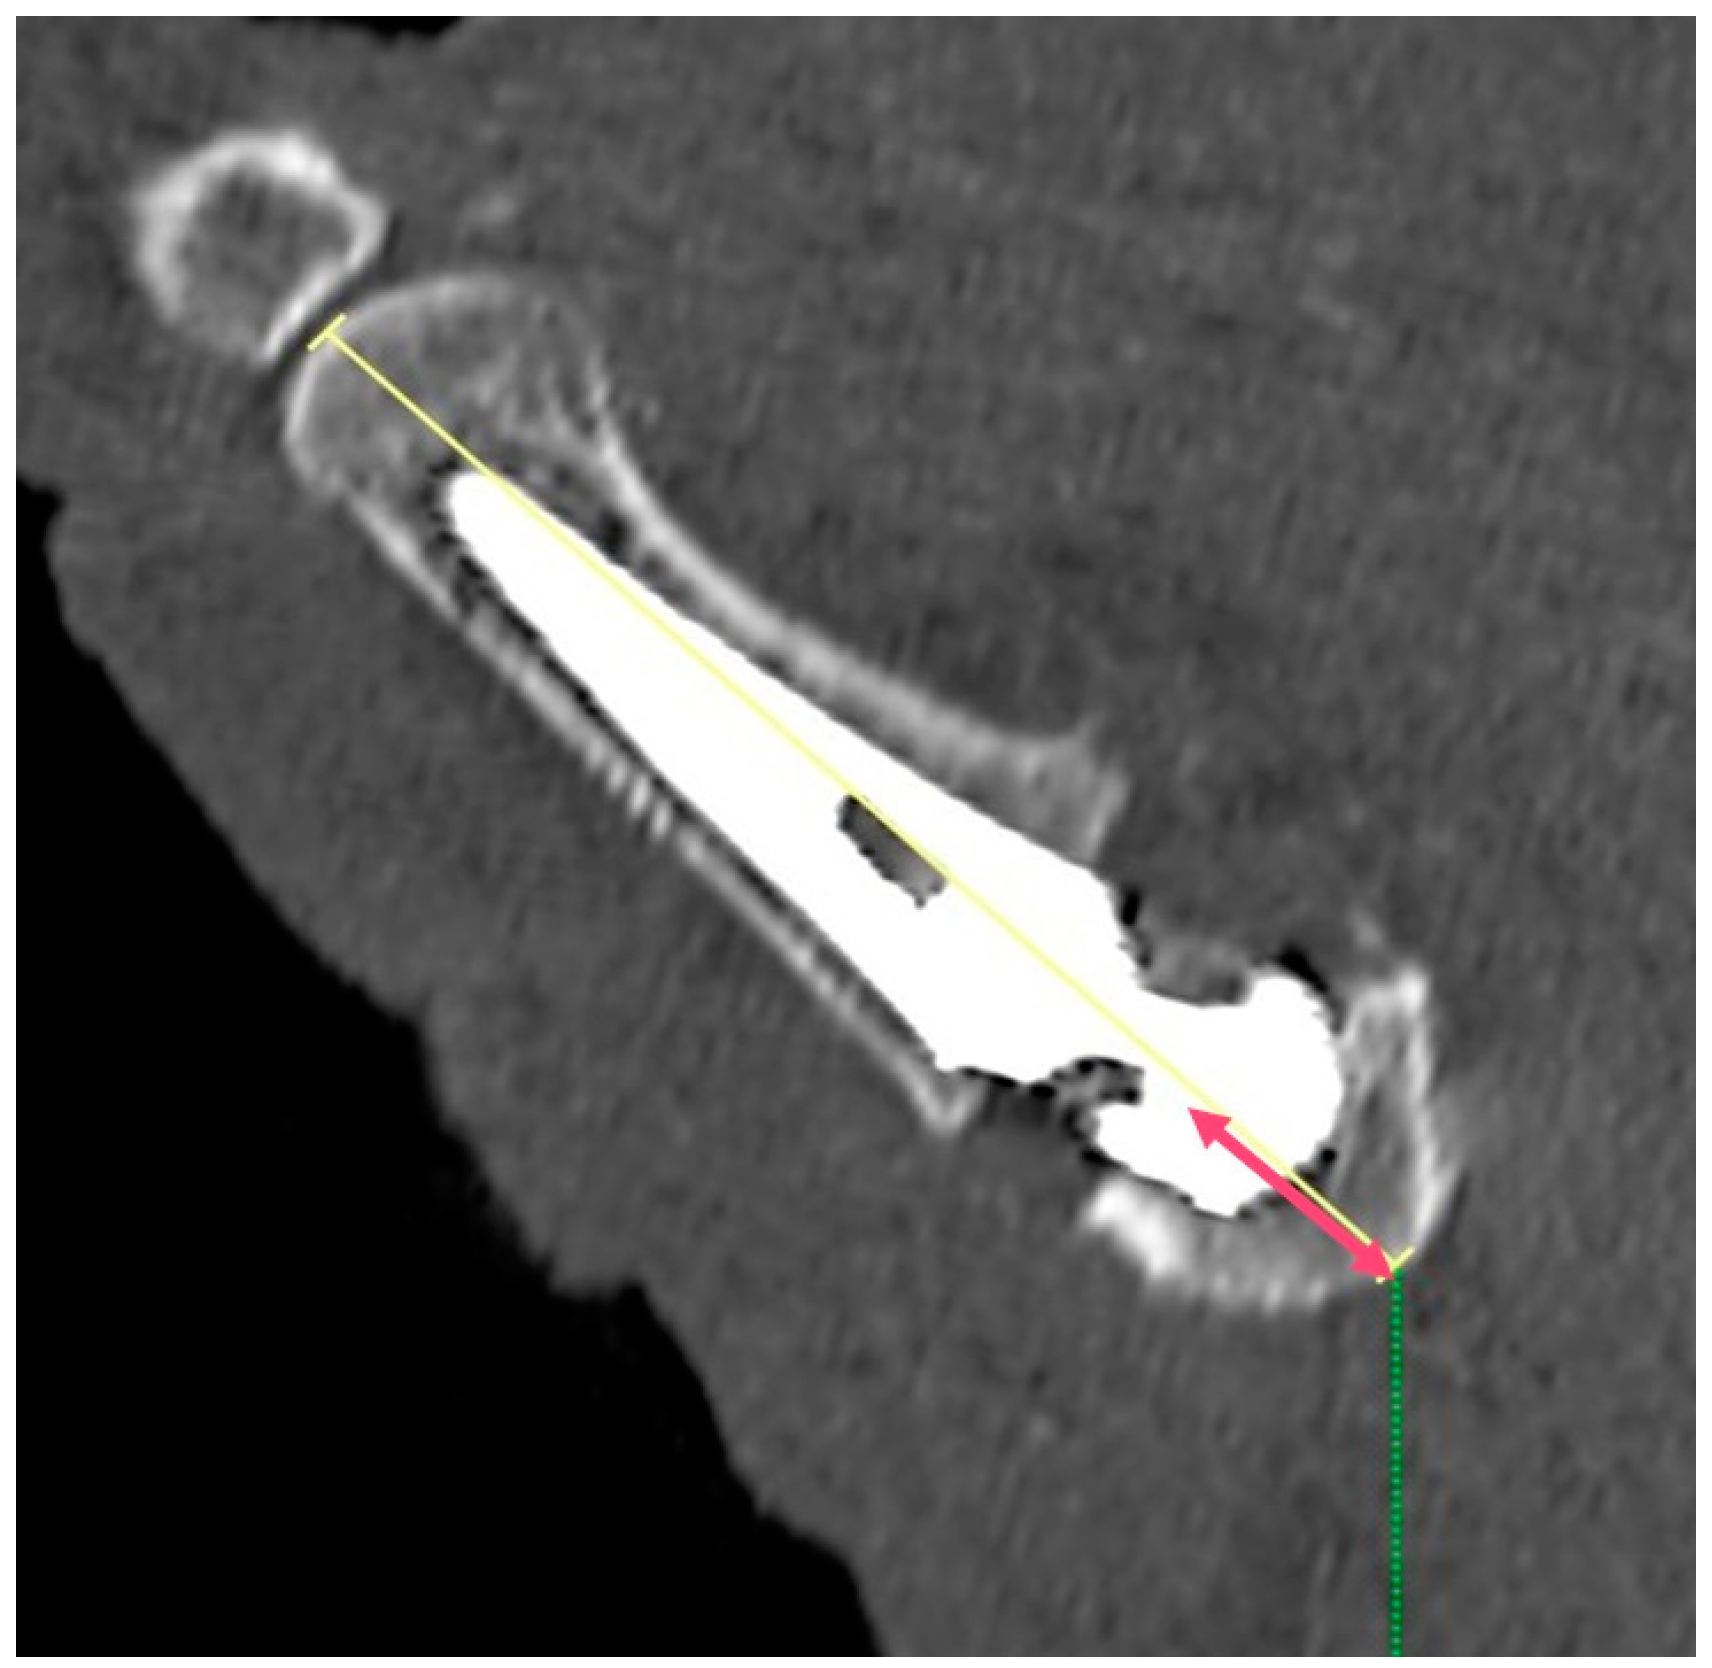

2.5. Imaging Analysis

3.1. CT Results

| Angle between the prosthesis axis and the M1 axis | 2.8° | ±1.3° |

| Angle between the cup distal surface and the trapezium | 2.0° | ±3.7° |

| Distance between the center of the trapezium and the center of the cup | 2.2 mm | ±1.3 mm |